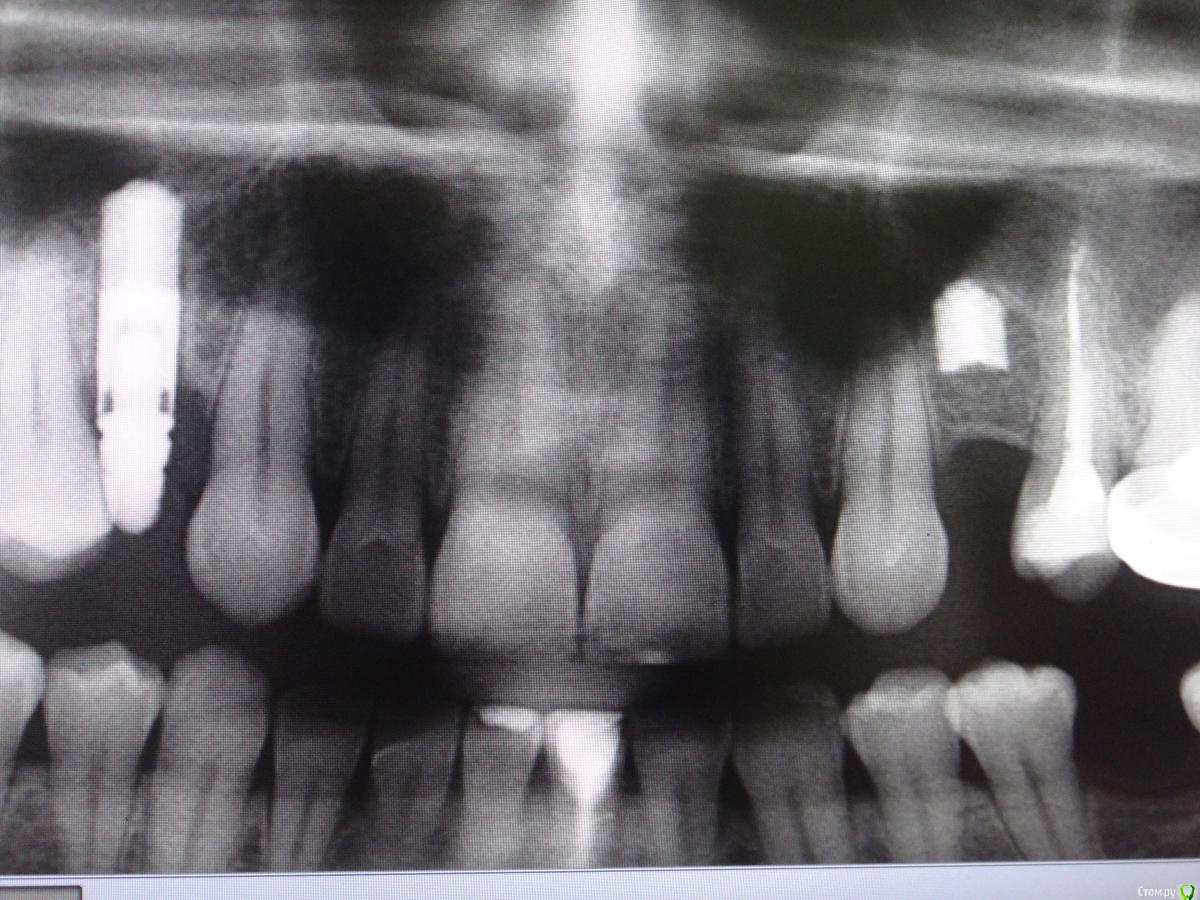

johniola Опубликовано 16 января, 2015 Поделиться Опубликовано 16 января, 2015 Мужики,что за импланты?от израиля ключи не подходят. Ссылка на комментарий

Alejandro Опубликовано 17 января, 2015 Поделиться Опубликовано 17 января, 2015 Хотя на mis seven сильно похожи Ссылка на комментарий

johniola Опубликовано 19 января, 2015 Автор Поделиться Опубликовано 19 января, 2015 узнал,это 3i , уже всё достал 2 Ссылка на комментарий

Kurz1981 Опубликовано 28 января, 2015 Поделиться Опубликовано 28 января, 2015 Похоже действительно Biomet3i http://whatimplantisthat.com/wp-content/uploads/2012/03/OSSEOTITE-Tapered-Certain-4.jpg Ссылка на комментарий